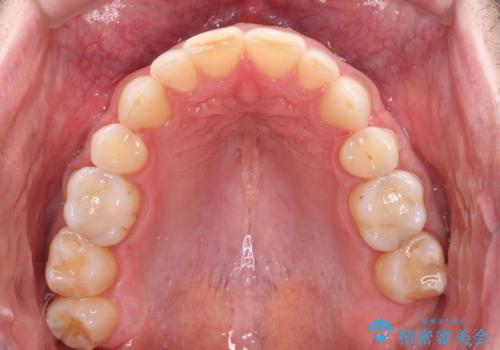

- 上下前歯の叢生を気にして来院された患者様です。

抜歯矯正をした後戻りということで、歯列不正はそれほど大きくなかったため、インビザライン・ライトを用いて矯正治療を行うこととしました。

前歯のデコボコが残っており、シミュレーション通りに動いていない部分がありましたが、再矯正であることやご本人の満足いくところまでデコボコが改善されたとのことで、治療を終了することとしました。